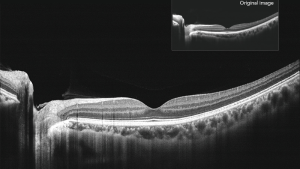

Кутовий аналіз 16 мм

Сканування від кута до кута 16 мм переднього відрізка з аналізом даних.